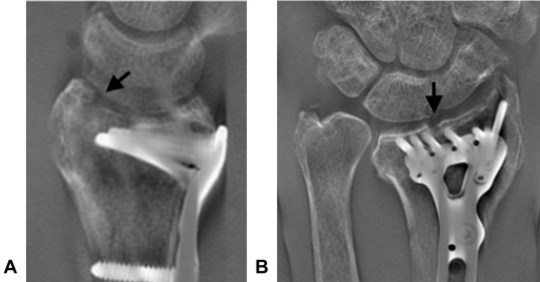

- Examinar la estabilidad de la reducción articular 12 semanas después de la fijación de la fractura del radio distal intraarticular (DRF) con una placa de bloqueo volar (VLP).

- No hubo cambios en la alineación de los fragmentos en los casos tratados con VLP.